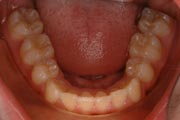

Crowding

After